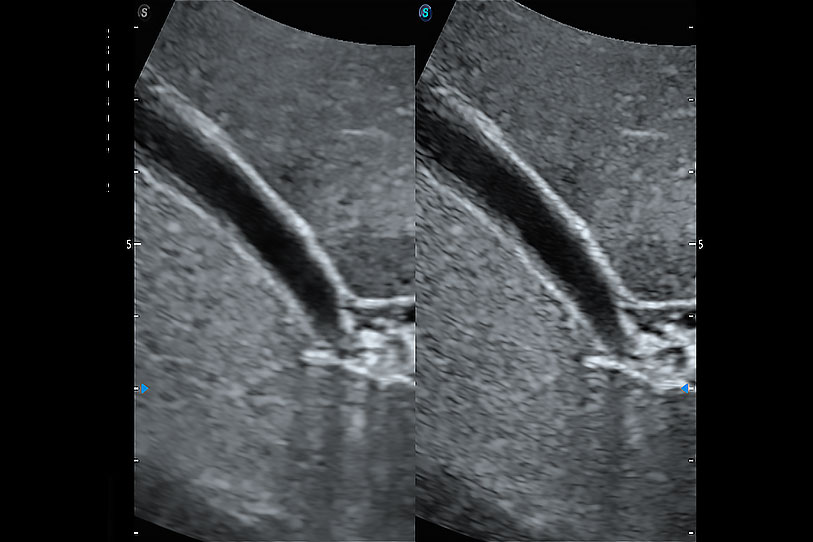

增強(qiáng)穿刺針在動(dòng)物解剖結(jié)構(gòu)中的位置,提高穿刺介入的安全性和準(zhǔn)確性。